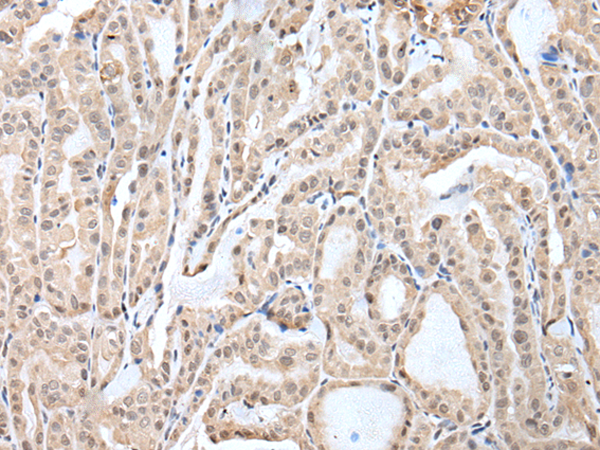

分类: 科研抗体货号: P12777别名: LRPB7应用: IHC反应种属: Human